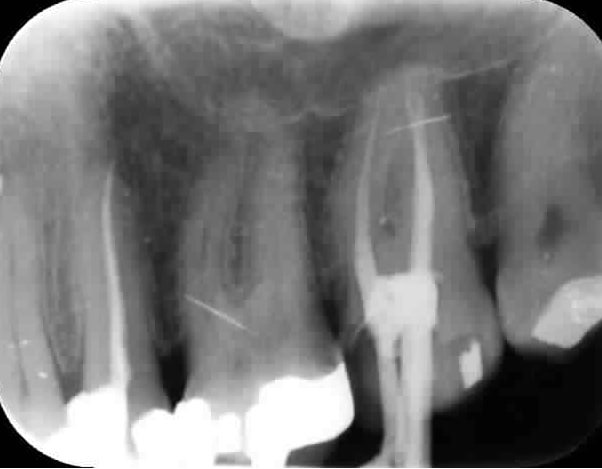

Bon, dans mon incommensurable mansuétude confraternelle, je me propose d'organiser un radiothon pour la praticienne de cosmite.

Un radiothon, comment, ca marche ?

Et bien c'est très simple Jacqueline...

Ex:

Cosmite a besoin d'une radio rétro-alvéolaire pré-op et post-op de 46 pour justifier un TTT endo, mais un soin deux faces doit être présent sur 47 !!

Chaque eugénolien va alors chercher dans sa base de donnée radio, les clichés pouvant se rapprocher au mieux de la situation décrite... après hop !! un ptit peu de toshop pour ajuster le tout et BIM !! Un bon cliché bien dans les clous qui fera le bonheur du CDC !!!

Tous ensemble, relevons le défi du radiothon de cosmite, pour élever toujours plus haut le niveau d'une profession à l'avenir radieux !!